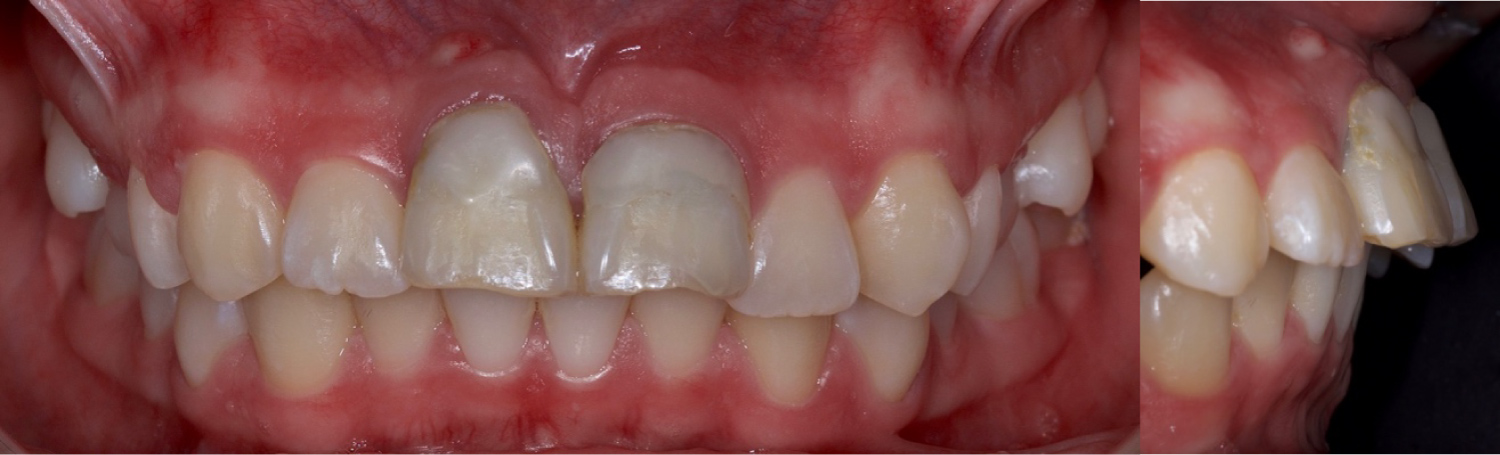

A 14-year-old female patient was clinically evaluated and presented the mobility of both maxillary incisors and was diagnosed as an endodontic-periodontal lesion due to recurrent infection (Figure 1).

Figure 1: Initial view (A) Frontal view; (B) Sagittal view. View Figure 1